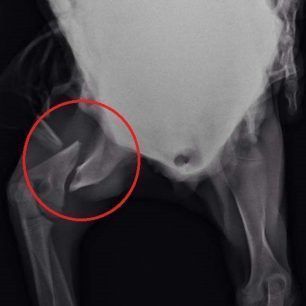

Το κουταβάκι που βλέπετε στις φωτογραφίες εντοπίστηκε χθες στο Άκτιο να κλαίει από τους πόνους κοντά στα διόδια της υποθαλάσσιας σήραγγας καθώς όπως αποδείχτηκε έχει σπασμένα τα δύο πόδια του ενώ είναι χτυπημένο και στην κοιλιά. Το πως τραυματίστηκε το ζώο παραμένει άγνωστο αν και σύμφωνα με τον κτηνίατρο Νίκο Ρώσσο, που το εξέτασε, κάποιος είναι πολύ πιθανό να το το κλώτσησε.

Η Δώρα Τσάτση μέλος του σωματείου «Παρέμβαση για τα Ζώα - Πρέβεζα» εξήγησε στο www.zoosos.gr ότι ο κ. Ρώσσος τους είπε πως είναι απίθανο το κουταβάκι, που ζυγίζει μόλις τέσσερα κιλά, να χτυπήθηκε από όχημα καθώς δεν έχει σημάδια και αυτά τα τραύματα προκαλούνται μόνο από κλωτσιά.

Εξαιτίας του νεαρού της ηλικίας του κουταβιού δεν θα γίνουν όλες οι επεμβάσεις ταυτόχρονα. Αρχικά θα χειρουργηθεί στην κοιλιά και στην συνέχεια θα ακολουθήσουν οι επεμβάσεις στο πίσω πόδι του που έχει σπάσει σε δύο σημεία και στη συνέχεια στο μπροστινό.